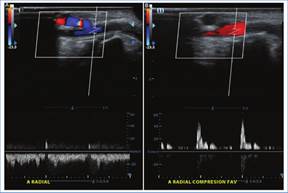

Los hallazgos ecográficos pueden ser:

Directos: ausencia de flujo en la evaluación Doppler color y espectral, falta de compresibilidad de la vena, visualización de material ecogénico endoluminal (según el estadio de evolución) (Fig. 2)3,4.

Indirectos: flujo de alta resistencia (tri- o bifásico) previo al sitio de trombosis y baja VPS posterior al sitio de trombosis3. Estos hallazgos pueden ser similares a los de una estenosis (Fig. 3)4.